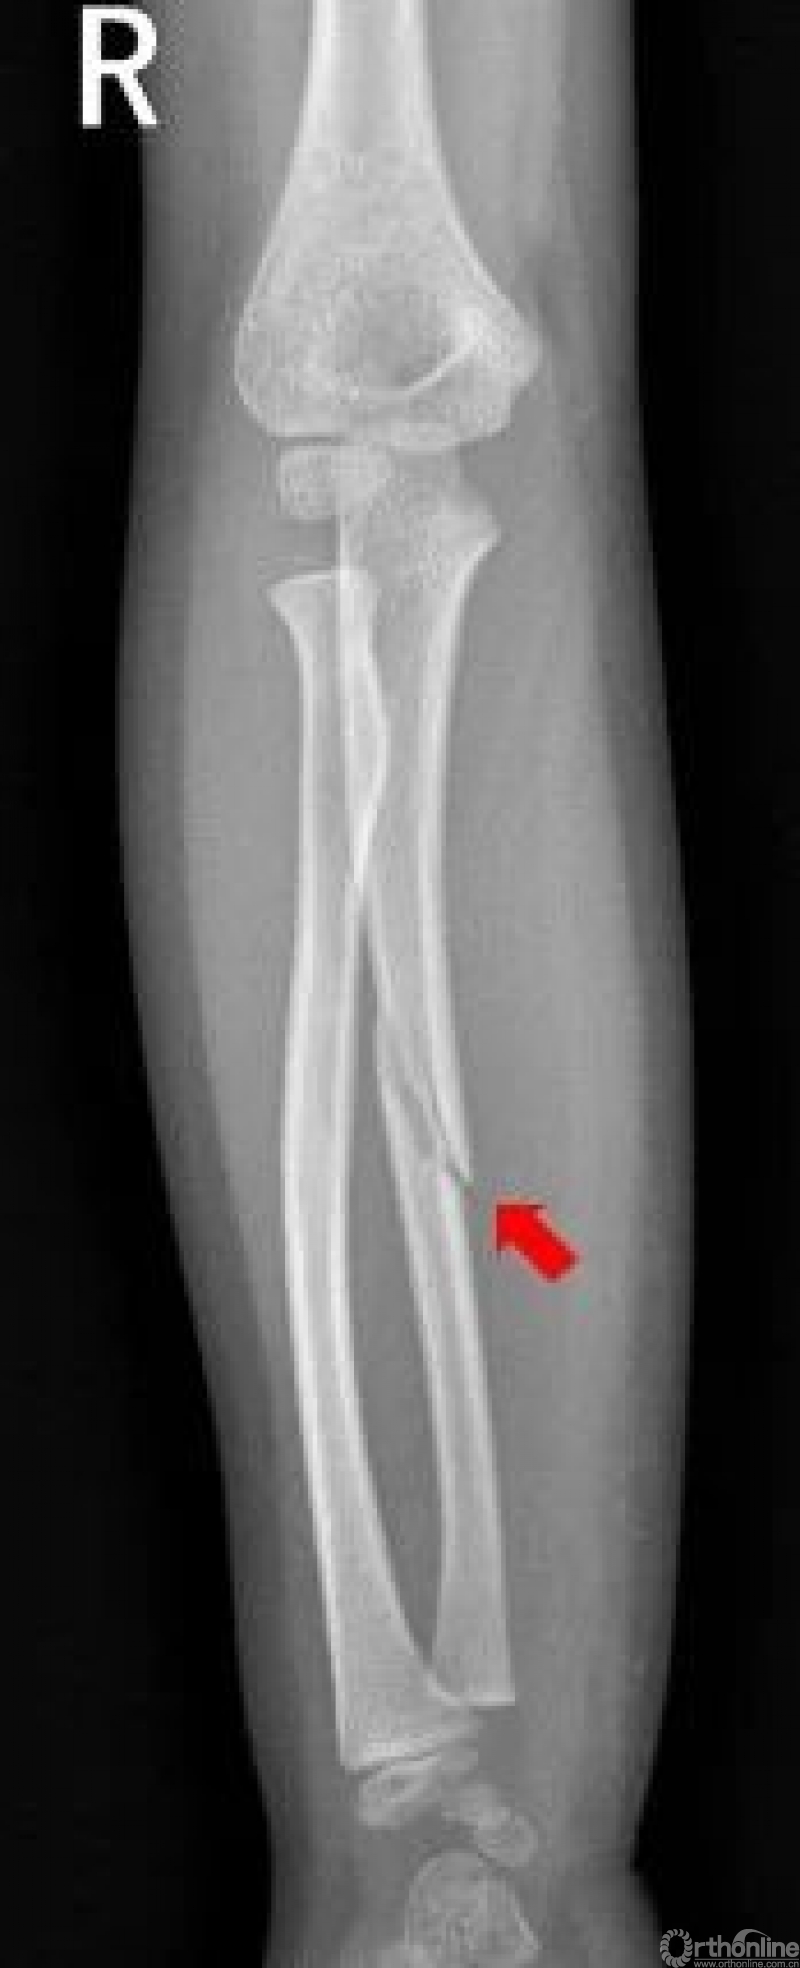

前臂

右侧尺骨中段可见斜形骨折线,骨折端稍分离移位。右侧尺骨中段骨折